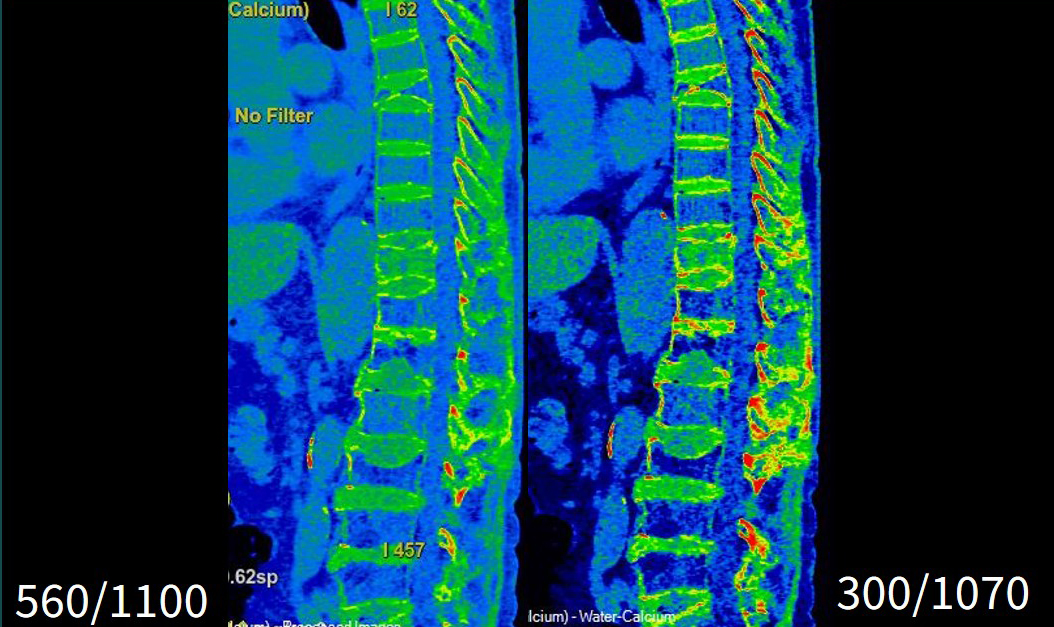

WW/WLの設定について

当院では胸腰椎圧迫骨折のDE画像として、70keVとWater(Calcium)(以下Wa(Ca))画像を作成しています。当初、 Wa(Ca)画像のWW/WLの表示条件については見た目の印象で決めていましたが、『GE HealthCareユーザーによるVNCa解析概要書』に記載されているWW/WLに変更すると、 Wa(Ca)画像のコントラストがつき観察しやすくなったので現在ではこちらの条件を採用しております(Fig4)。ただし、患者の年齢や症例によっては従来通りWWを広げた方が観察しやすい場合もあり適宜調整していく必要があります。

AWではレイアウトを設定していますので、開くと指定のカラー、WW/WLのWa(Ca)画像で立ち上がります。立ち上げて範囲だけを決め、保存を行っています。

Frontier_Wakkanai04.jpgFig4. 従来のWW/WL(左)と概要書のWW/WL(右)の比較